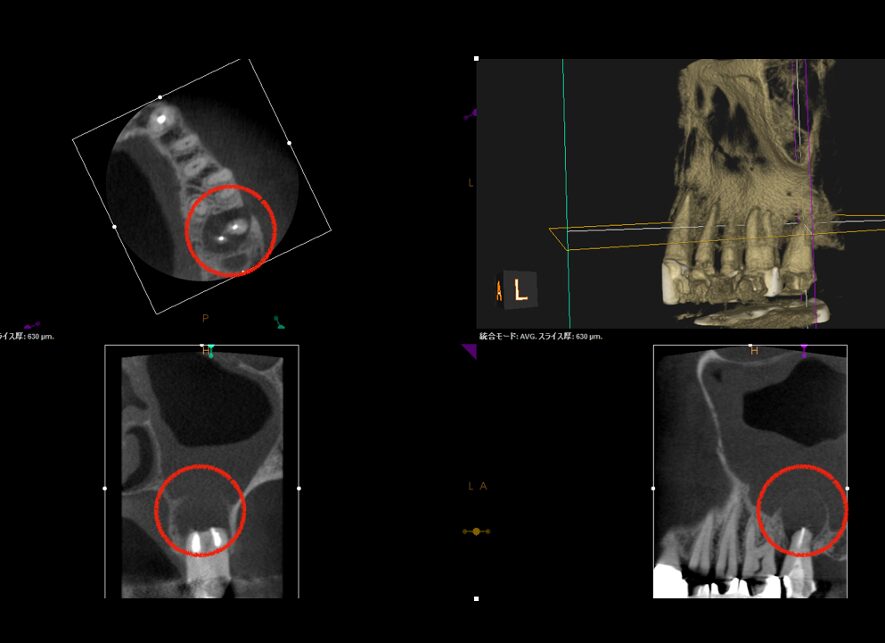

術前CT画像。赤丸が病変で、上顎洞炎の併発も確認できる

当院で精密根管治療を施しましたが、瘻孔(フィステル・サイナストラクト)を消失させることが難しく、追加処置として歯根端切除術(今回は意図的再植術)を行いました。また、術前に撮影したCT画像より、根尖性歯周炎が原因と考えられる上顎洞炎(蓄膿症/ちくのうしょう)の併発も確認できました。